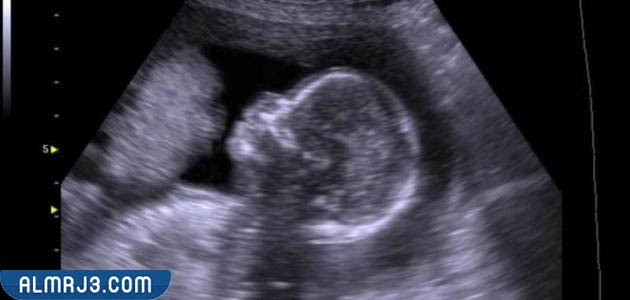

الكشف عن جنس الجنين بواسطة السونار

يمكن اللجوء إلى جهاز السونار لتحديد جنس الجنين في الأسبوع 15 أو 16 من الحمل، وذلك لأن الأعضاء التناسلية الخاصة بالجنين تكون قد اكتملت في هذه الفترة من الحمل، وتجدر الإشارة إلى أن أجهزة السونار أو الموجات الفوق صوتية لا تؤثر بشكل سلبي على الجنين مثلما تفعل الكثير من الأجهزة الأخرى، ولكن يحتاج هذا الجهاز إلى الانتظار لفترة من الوقت حتى يتم تحديد جنس الجنين بدقة عالية، إذ يخجل الكثير من الأجنة عن الحركة مما يحتاج إلى تحريك الجهاز حتى يقوم الطفل بتحريك أعضاؤه، وتجدر الإشارة إلى ضرورة مليء المثانة بكمية كافية من الماء قبل الإقبال على جهاز السونار لتحديد جنس الجنين، ويساعد ذلك الأمر في التعرف على جنس الجنين بدقة ووضوح.